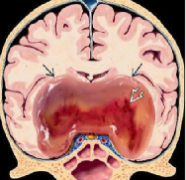

脑脊液动力学百年经典理论争议-国际小儿神外教科书教授谈脑积水新病理机制